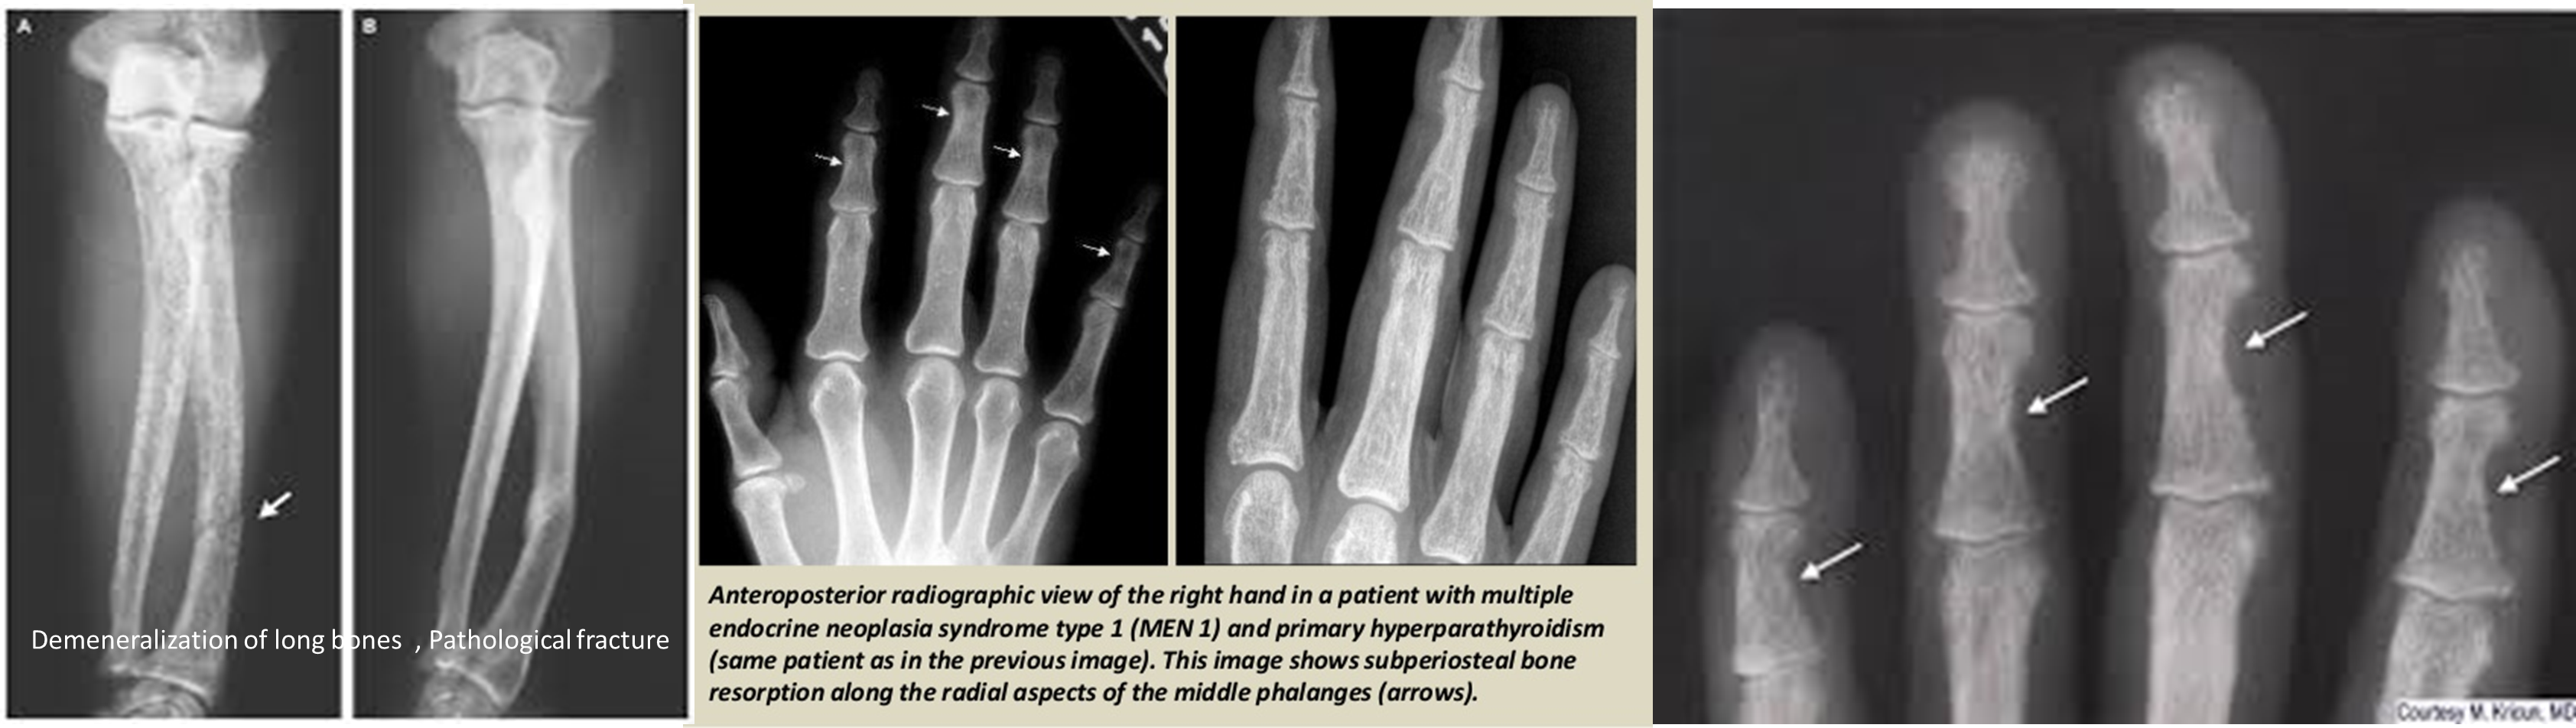

Radiological Features

Characteristic X-ray Findings

- Sub-periosteal bone resorption (most specific finding)

Comprehensive Radiological Manifestations

- Bone changes:

- Rarefaction (generalized osteopenia)

- Bone resorption patterns:

- Sub-periosteal resorption: middle phalanges, tibial shaft

- Lateral end of clavicle resorption

- “Brown tumors”: (coagulated blood-filled cystic spaces)

- Skull: “salt & pepper” appearance

- Soft tissue calcification

Radiology:

- DEXA: Wrist, spine, and hip

- KUB, IVP, CT (For renal stones)

DEXA: Dual Emission X-ray Absorptiometry Demineralization of long bones, Pathological fracture

Lytic lesions caused by hyperparathyroidism are called Brown tumors. The term “Brown tumor” is a misnomer because it is not a true neoplasm.

Lytic lesions caused by hyperparathyroidism are called Brown tumors. The term “Brown tumor” is a misnomer because it is not a true neoplasm.

Radiological features of hyperparathyroidism

- In hand, sub-periosteal bone resorption .This change usually happen in the middle phalanges, radial aspect in the 2nd or 3rd finger.

- Terminal tuft erosion.

- Salt and pepper skull

Sub-periosteal bone resorption

- Most useful sign

- Virtually Diagnostic

- Location

Subperiosteal bone resorption (straight arrow), resorption of the tip of the terminal phalanx and the altered bone architecture. Arterial calcification is also present (curved arrow).